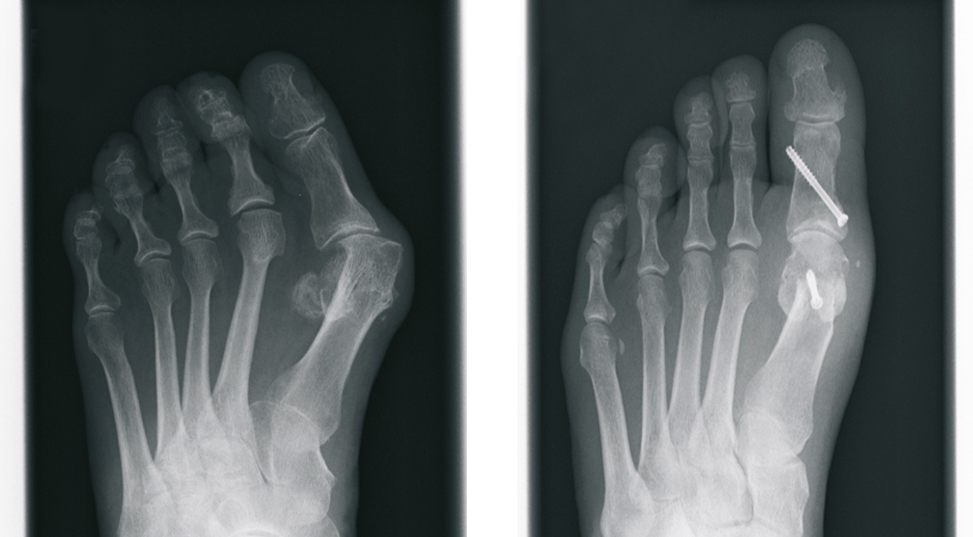

The Hallux valgus (balltoe)

Hallux valgus - in linguistic usage frequently called ball toe - concerns a deviation of the large toe outward, small toes upward. This deformity is more common by women. The exact Cause is not clarified, of course wrong Footwear and hereditary factors play a large role. The different versions are marked by increased deformity and accompanied by pain.

Surgical correction without the presence of pain is not advisable from a purely cosmetic point of view. However, In case of pain in the big toe, the operative procedure is the only permanent therapeutic option.

After extensive examination, consideration of individual needs, as well as analysis of the X-ray images, the treatment is determined. Different internationally recognized surgical procedures are used. We use modern plates and titanium screws.